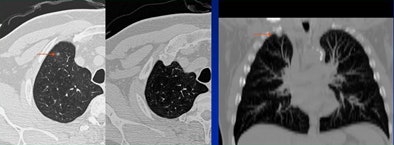

|  |

| Decision-making error: Lung mass (arrow, left) was called as a pulmonary artery. All images courtesy of Dr. Charles White. |